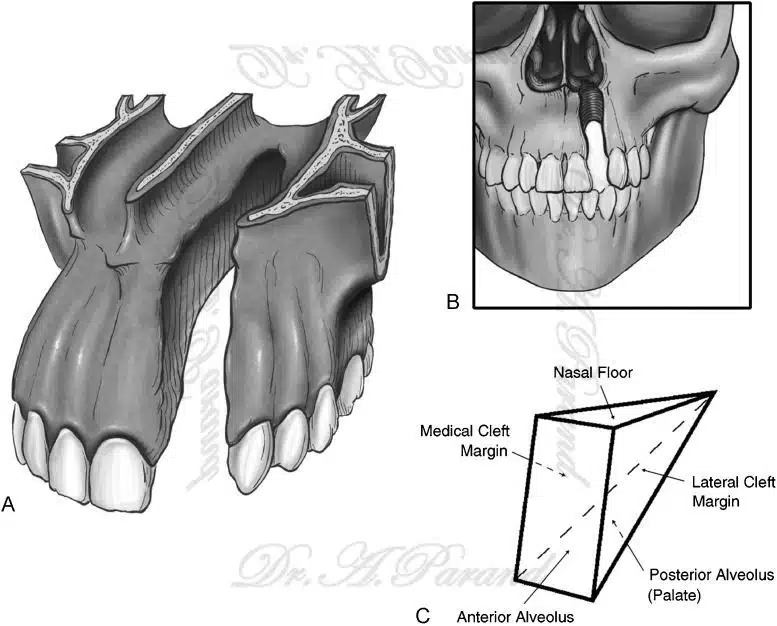

شکاف آلوئولار یکی از مشکلات رایج در کودکان است که میتواند به مرور زمان سبب بروز مشکلات جدی در سلامت دهان و دندان شود. این مشکل نیاز به تشخیص دقیق و مشاوره با فوق تخصص جراحی پلاستیک دارد تا بتوان بهترین راهحلهای جراحی را برای درمان آن انتخاب کرد. در این مقاله دکتر علی پرند فوق تخصص جراحی پلاستیک زیبایی و ترمیمی به بررسی انواع روشهای جراحی برای اصلاح شکاف آلوئولار، مزایای هر روش و نکات مهم در مراقبتهای پس از جراحی پرداخته خواهد شد. همچنین به سوالات متداول در مورد این نوع جراحی پاسخ داده میشود تا خوانندگان با اطلاعات کاملتری تصمیمگیری کنند.

روشهای مختلف جراحی شکاف آلوئولار میتواند شامل تکنیکهای گوناگونی باشد که هرکدام با توجه به شرایط بیمار و نوع شکاف انتخاب میشوند. این روشها به منظور بازسازی و بهبود ساختاری و عملکردی ناحیه آلوئولار انجام میگیرند.

شکاف آلوئولار چیست؟

شکاف آلوئولار یک نقص مادرزادی است که در آن بخشی از دهان و فک بالا بهطور کامل تشکیل نمیشود. این شکاف معمولا بین دندانها و لثهها قرار دارد و ممکن است به بینی نیز متصل باشد. این مشکل میتواند به مشکلات تغذیه، گفتار و حتی تنفس منجر شود.

جراحی شکاف آلوئولار چگونه انجام میشود؟

جراحی شکاف آلوئولار هدف دارد که نقص موجود را اصلاح کند و عملکردهای دهان و فک را بهبود بخشد. این جراحی معمولا در چند مرحله انجام میشود و شامل استفاده از بافتهای بدن خود فرد برای پر کردن شکاف و بازسازی ساختار دهان و فک است.